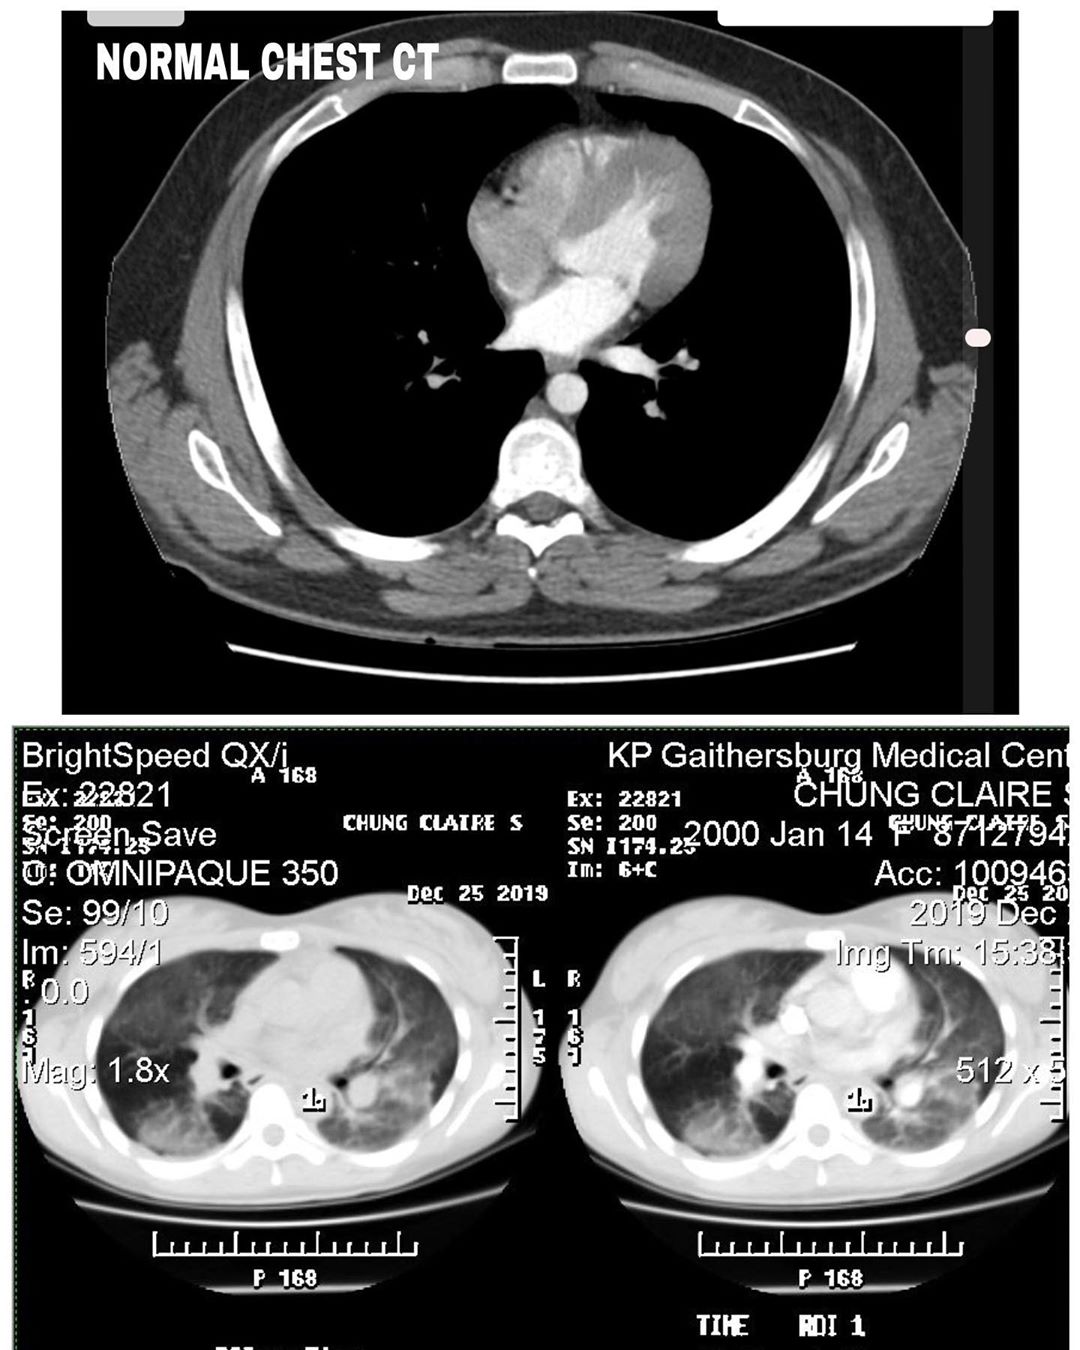

由于病情持续恶化,Claire 就在圣诞节早上进入了急诊室。但医生却一直找不到病因,直到电脑断层扫描(CT Scan)肺部后,才发现Claire 的肺一片浑浊灰白,而且完全覆盖了两个肺。

Claire 之后在 Instagram 上传她的电脑断层扫描结果,从这些X光片中可以看到,正常的肺是黑的,但她的肺已经变成是一片混浊而且发白的。

▼ 图 ③(上图为正常的肺,下图为 Claire 的检查结果。)